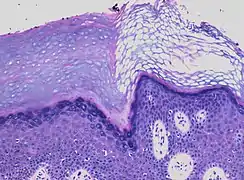

In contrast, hyperkeratosis (pictured) may also show a heterogeneous stratum corneum, but a preserved granular layer is seen.